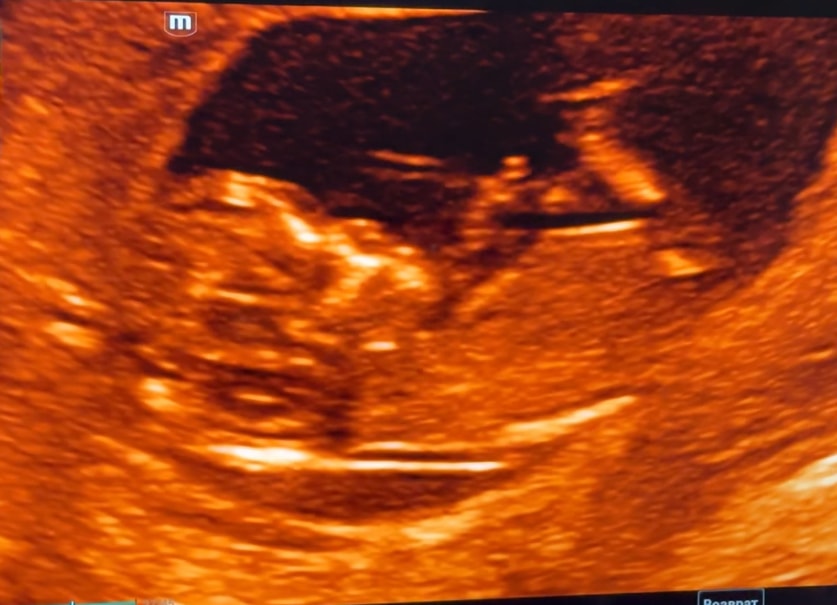

Так прикольно что я 2 прошлых сюда заливала, и можно посмотреть и сравнить ) все в порядке, сдала кровь, еще завтра иду платно на экспертное узи 🙌🏻 Всегда делаю 2 раза, первое от ЖК, хоть и в крутом ПЦ, второе экспертное узи у топ врачей, все же доверяй но проверяй)